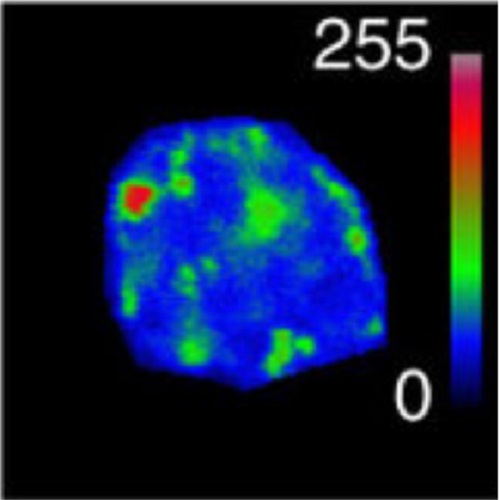

During mammalian cerebral cortex development, the G1-phase of the cell cycle is known to lengthen, but it has been unclear which neural stem and progenitor cells are affected. In this paper, we develop a novel approach to determine cell-cycle parameters in specific classes of neural stem and progenitor cells, identified by molecular markers rather than location. We found that G1 lengthening was associated with the transition from stem cell-like apical progenitors to fate-restricted basal (intermediate) progenitors. Unexpectedly, expanding apical and basal progenitors exhibit a substantially longer S-phase than apical and basal progenitors committed to neuron production. Comparative genome-wide gene expression analysis of expanding versus committed progenitor cells revealed changes in key factors of cell-cycle regulation, DNA replication and repair and chromatin remodelling. Our findings suggest that expanding neural stem and progenitor cells invest more time during S-phase into quality control of replicated DNA than those committed to neuron production.

Fig.6 taken from Arai et al, 2011.